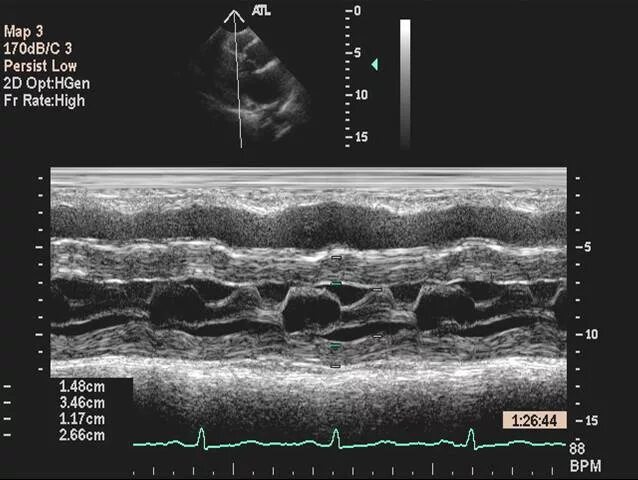

M mode